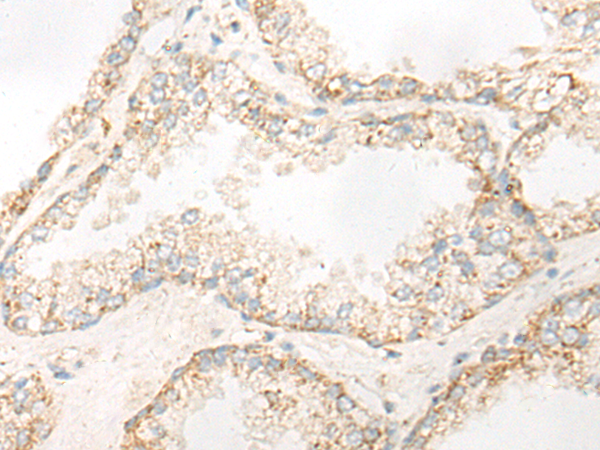

分类: 科研抗体货号: P06380别名: RRP44; dis3p; EXOSC11; KIAA1008; 2810028N01Rik应用: IHC反应种属: Human